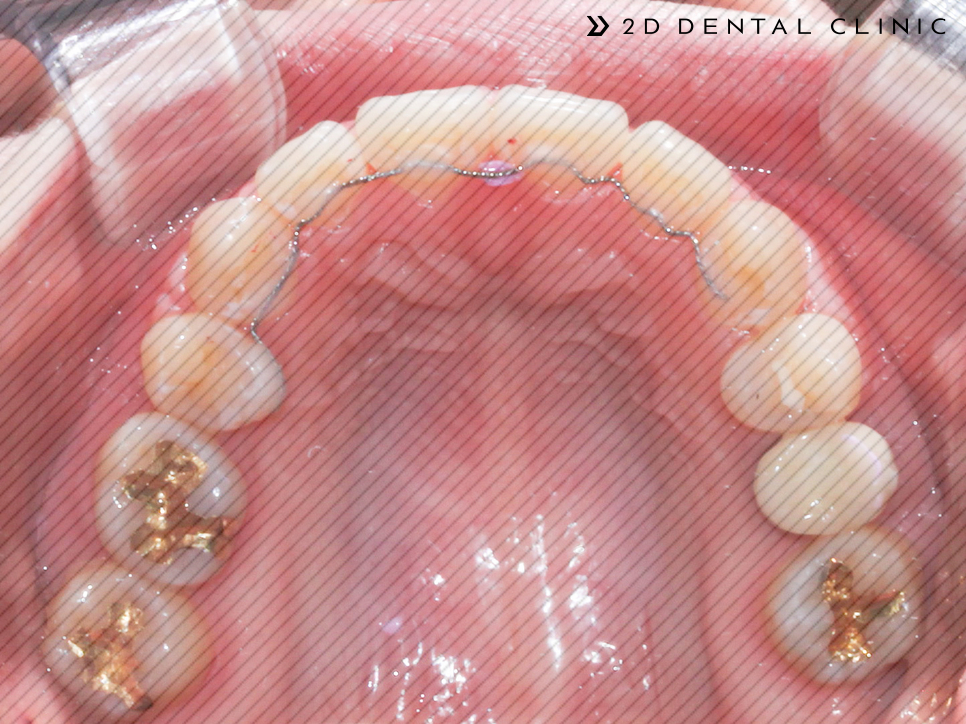

다시 전후 케이스 리뷰로 돌아와서! 본 환자분은 심한 크라우딩 상태에 상악의 제1 대구치(첫 번째 큰 어금니)가 없으신 상태셨답니다.

제1 대구치 자리에 제2 대구치를~

빈 공간을 임플란트로 채울 수 있는 옵션이 있지만 제1대구치 자리에 제2 대구치를 당겨서 빈자리를 채울 수 있게 진행했습니다.

전체 교정인 클리피씨로 진행되었고 상악의 양쪽의 제1소구치를 발치하였습니다. 제2 대구치는 미니스크류로 당겨드렸고요.

전체적인 크라우딩의 개선

교정기간은 1년 반이 소요되셨답니다~ 전체적인 크라우딩이 개선되고 치아 배열이 고르게 개선되었습니다.